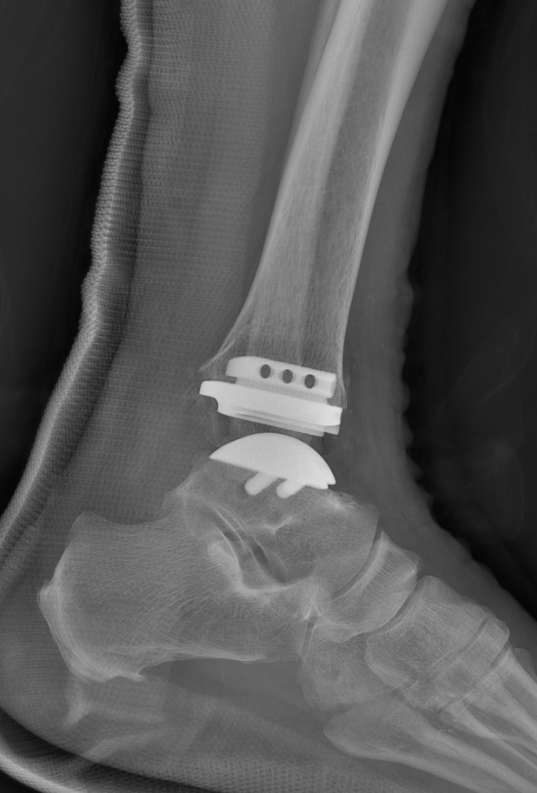

武勇主任团队给他做了3D打印导板辅助下人工全踝关节置换术。

这种手术适合踝关节病严重的患者,通过替换病变的关节结构,能帮着缓解疼痛、恢复关节活动,让老人日常走路更自在些。

术后侧位X线

术后正位X线

在北京积水潭医院武勇主任的带领下,北京积水潭医院郑州医院足踝外科团队严格照着阶梯治疗的规范来,还结合了3D打印这样的技术。

3D打印导板能让手术操作更精准,减少术中创伤、缩短手术时间,也为患者术后恢复打下好基础。